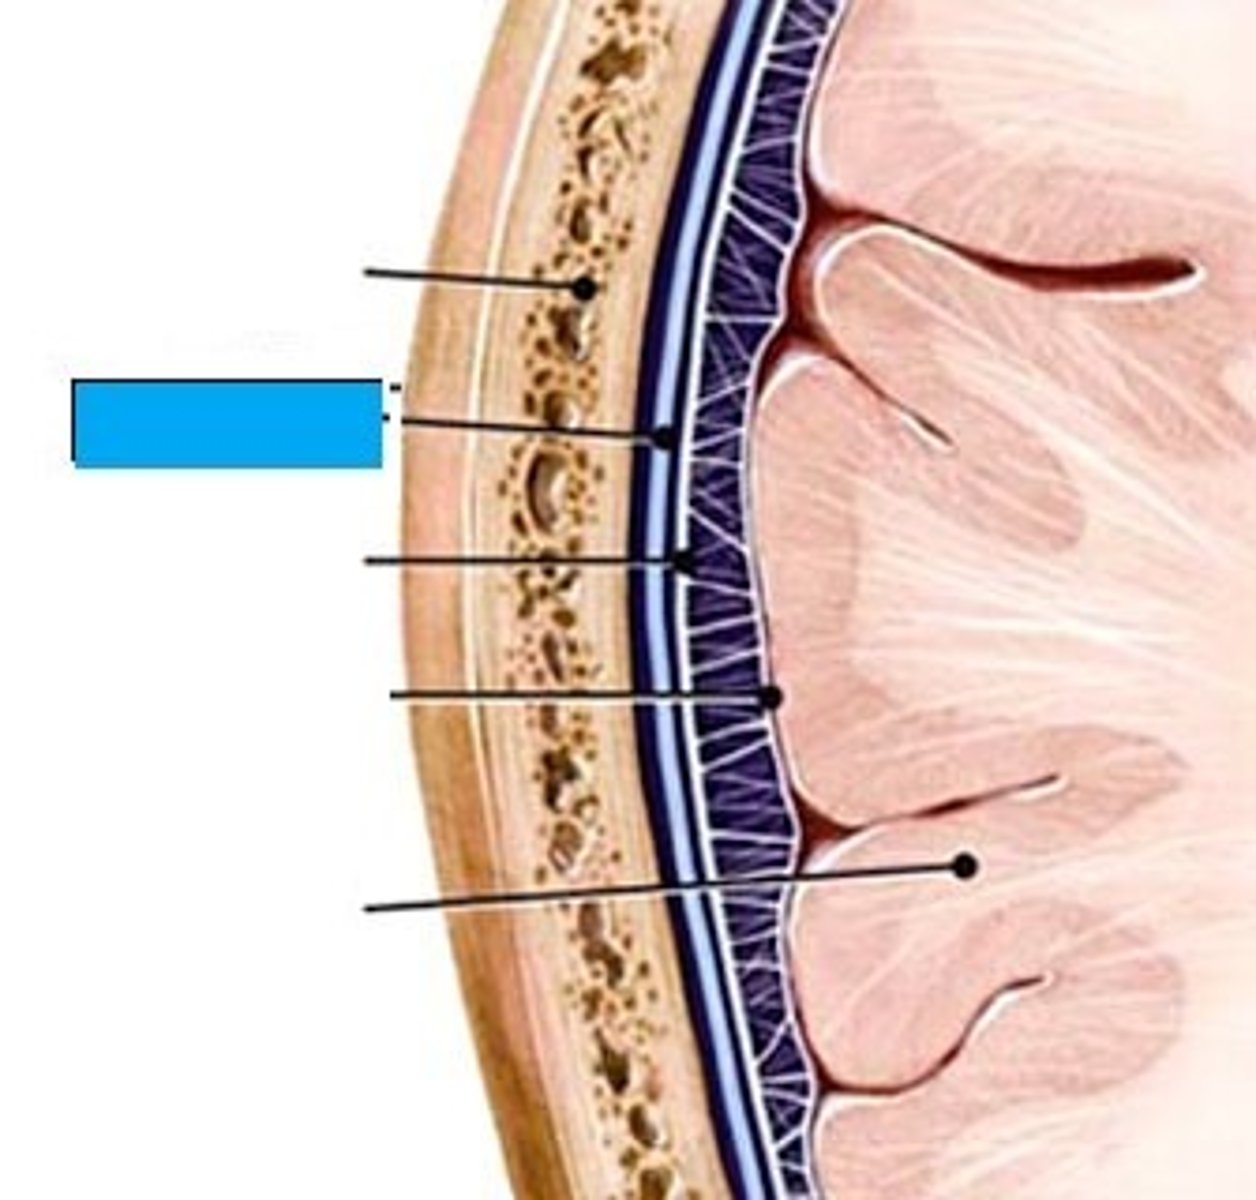

dura mater

periosteal layer

meningeal layer

arachnoid mater

subarachnoid space

with arachnoid trabeculae

pia mater

tentorium cerebelli

falx cerebri